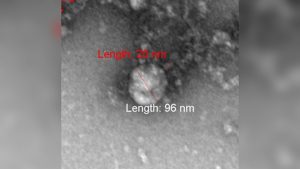

Роспотребнадзор показал первое фото британского штамма коронавируса

Роспотребнадзор показал первое фото британского штамма коронавируса

Ученые ФБУН ГНЦ «Вектор» Роспотребнадзора первыми в мире сфотографировали штамм коронавируса, выделенный в Великобритании.

Изображение удалось получить с помощью трансмиссионного электронного микроскопа. Вирусная частица обладает округлой формой и типичными для коронавируса колбообразными пепломерами (спикулами).

В...